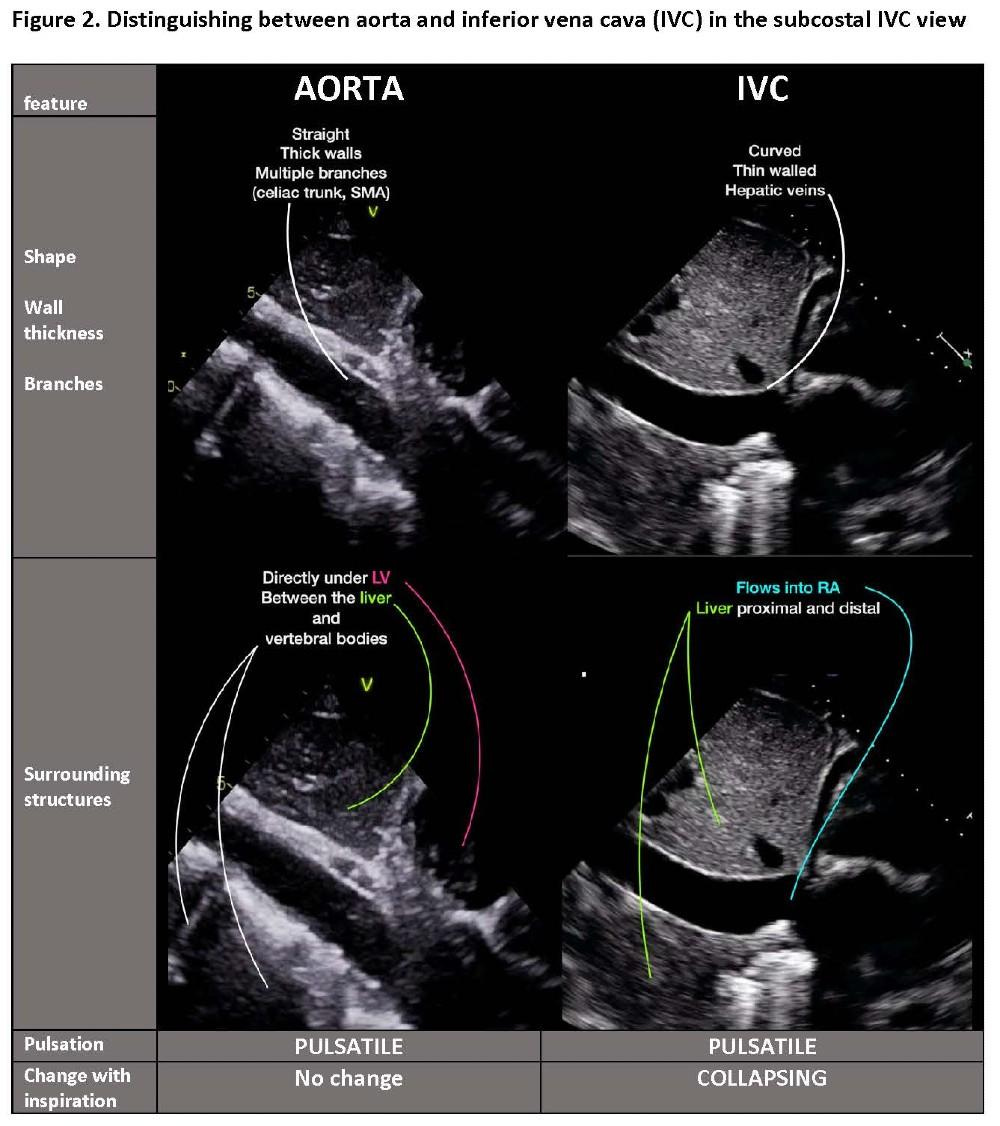

Step 1: Inferior Vena Cava (IVC)

How to Obtain the View

Place probe subxiphoid using liver as window

Start with short-axis view (marker at 3 o’clock)

Identify IVC within liver (right side), aorta midline

Rotate to long axis (marker at 12 o’clock)

Visualize IVC entering right atrium and hepatic vein junction

Short-Axis Importance

The short-axis view avoids the “cylinder effect” of long-axis imaging and provides a true cross-sectional representation. It also allows qualitative assessment of a plethoric, circular IVC, which may better reflect elevated RAP, particularly in Asian populations .

Pitfalls

Confusing IVC with aorta

Cylinder effect (long axis underestimation)

Collapsed IVC despite high RAP (raised intra-abdominal pressure)

Dilated IVC in athletes

Misinterpretation using a single view